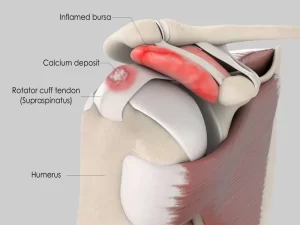

رسوب کلسیم در تاندون ها یا تنسون کلسین، همانطور که از نامش پیداست، پدیدهای پزشکی است که در آن کلسیم در تاندون های بدن به